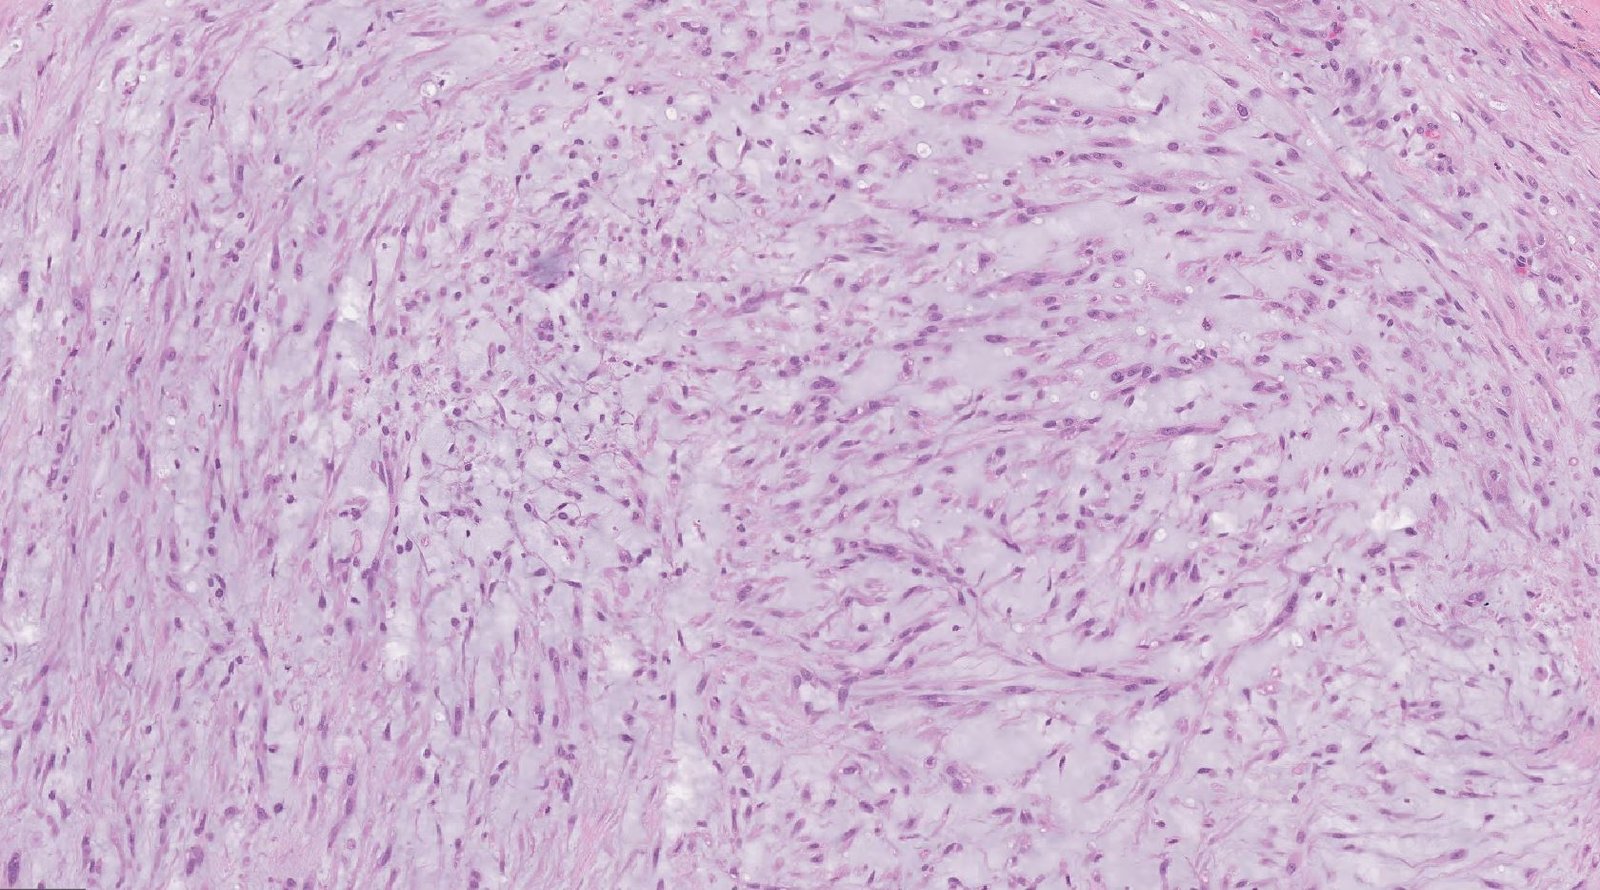

Case: ThighMass4